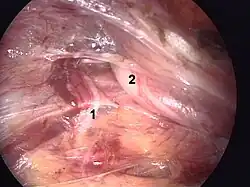

Laparoscopic repair

There are two main methods of laparoscopic repair: transabdominal preperitoneal (TAPP) and totally extra-peritoneal (TEP) repair, and these have been demenstrated to yield similar outcomes.[65] When performed by a surgeon experienced in hernia repair, laparoscopic repair causes fewer complications than Lichtenstein, particularly less chronic pain. However, if the surgeon is experienced in general laparoscopic surgery but not in the specific subject of laparoscopic hernia surgery, laparoscopic repair is not advised as it causes more recurrence risk than Lichtenstein while also presenting risks of serious complications, as organ injury. All that said, many surgeons are shifting to using laparoscopic techniques as they require smaller incisions, and result in less bleeding, lower infection rates, faster recovery, shorter hospitalization periods, and reduced chronic pain.[66][67]